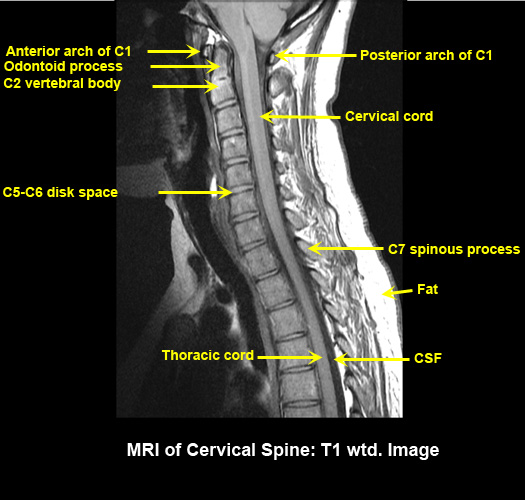

MR Brain and Spine